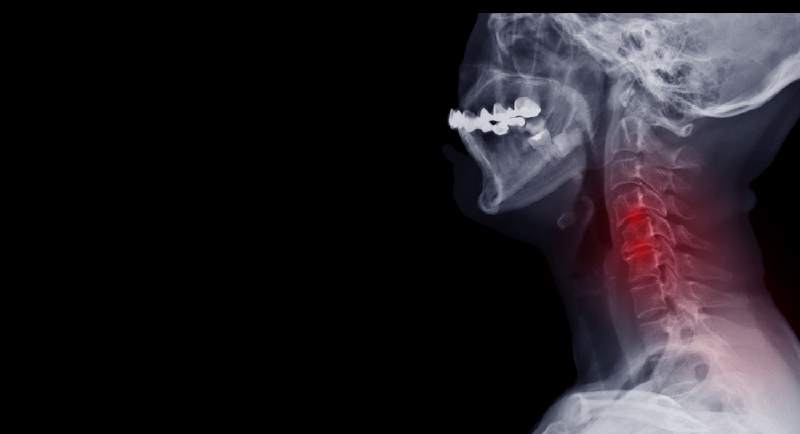

Stenoza szyjna, znana również jako zwężenie kręgosłupa szyjnego, jest stanem, w którym dochodzi do zwężenia kanału kręgowego w odcinku szyjnym kręgosłupa. Kanał kręgowy zawiera rdzeń kręgowy oraz nerwy, które wychodzą z niego i zaopatrują ręce, szyję i górną część ciała. Stenoza szyjna może prowadzić do ucisku na te struktury, powodując ból, drętwienie, osłabienie i inne objawy.